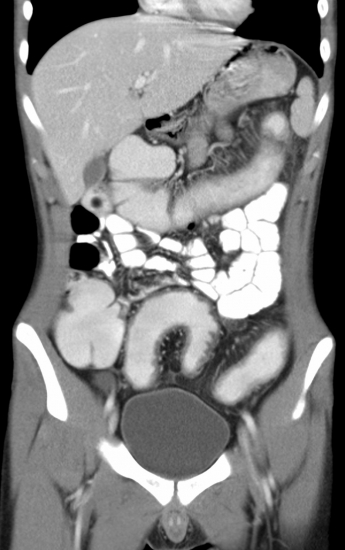

Der Kurs diente explizit zur Vorbereitung für das schriftliche Examen. Hierzu besprachen die Referenten viele verschiedene Multiple-Choice-Fragen mit radiologischem Bildmaterial. Abgedeckt wurden Themengebiete wie z. B. Thorax, Neuroradiologie, Angiographie, Urogenitaltrakt und mehr. Passend zur entsprechenden Röntgen-, CT- oder MRT-Aufnahme erklärten die Radiologen, welche Informationen sich aus den bildgebenden Modalitäten gewinnen lassen und natürlich auch, auf welchem Weg man die Examensfrage lösen kann.

Häufig zeigten die Referenten, wie sich falsche Antwortmöglichkeiten allein mit logischem Denken ausschließen lassen. Eine Jejunalstenose könne beispielsweise in einem Röntgenbild nicht vorliegen, wenn der Colon luftgefüllt ist.